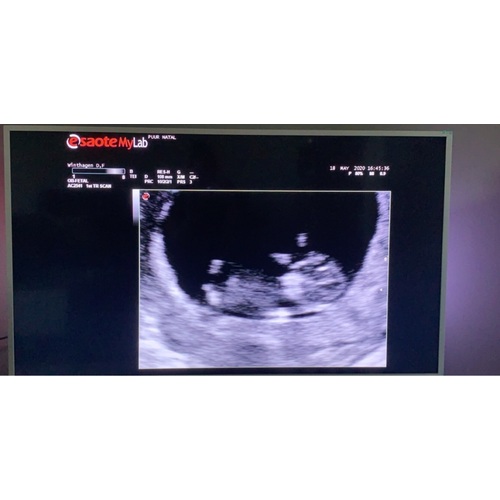

Wie durft een gokje te wagen? Ik ben benieuwd :)

Echo is van 12+4 dagen. Over 4 weekjes weet ik het!

Liefs

Meisje

Ik hou het op jongen 馃挋馃槉